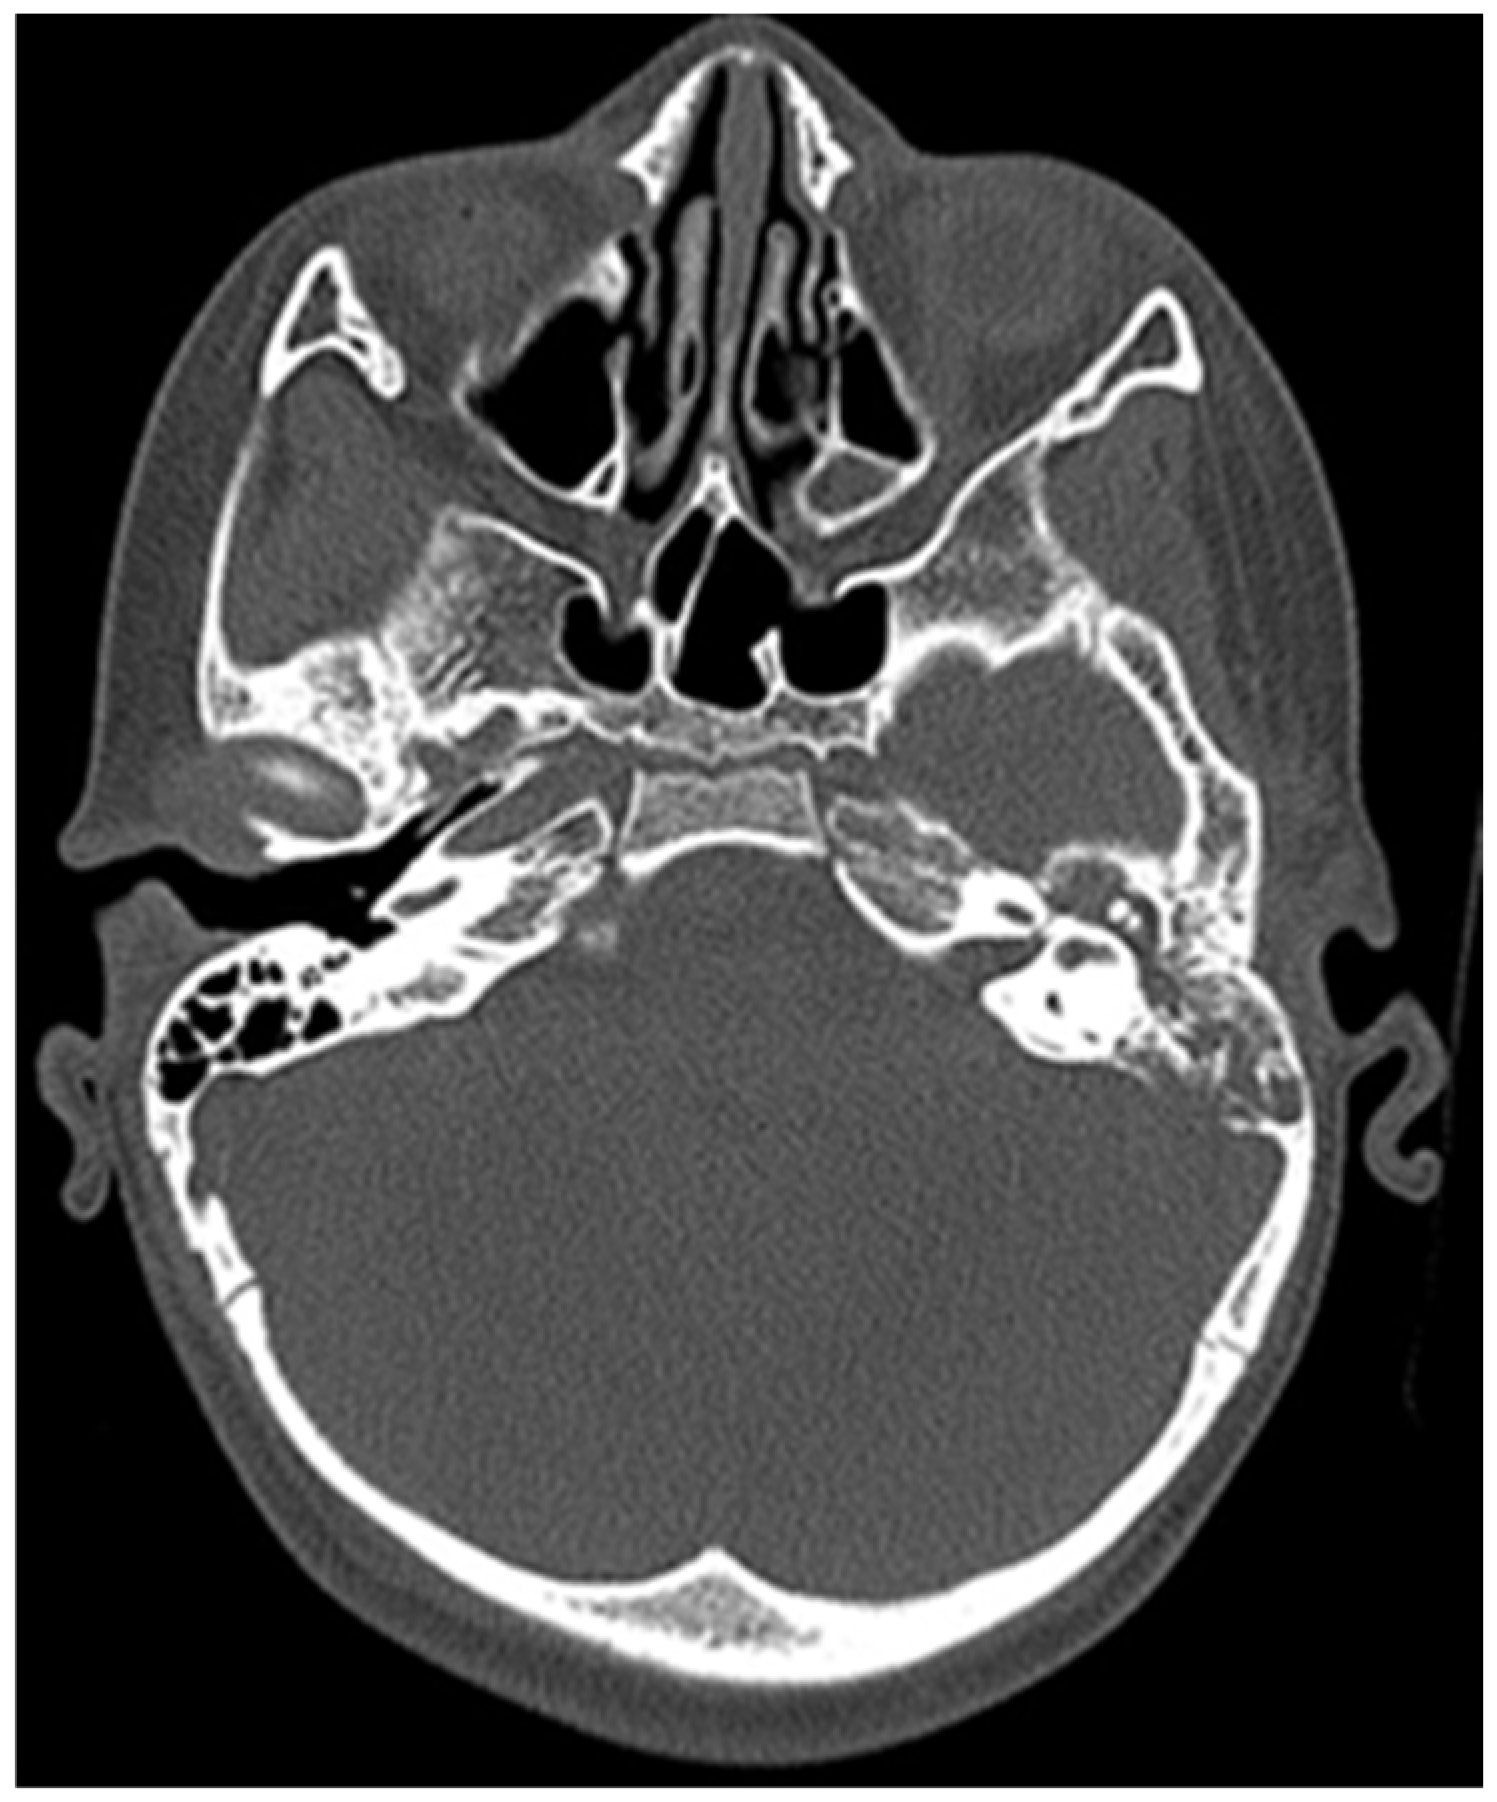

CT of the head was performed, which showed destruction of the left mastoid process from a soft tissue tumour mass, which involves the cavities of the middle ear, tympanic cavity and the external auditory channel (Figure 2 and Figure 3).

Figure 2. Initial CT of the patient.

Figure 3. Initial CT of the patient.

After these CT findings, an examination by an ENT specialist was performed—left external auditory canal was completely obstructed by a soft tissue formation, which resembles granulation tissue, left tympanic membrane was impossible for observation. Second diagnosis was established—peripheral facial nerve palsy, caused by middle ear chronic inflammation. So the patient was transferred to an ENT clinic for surgical treatment.